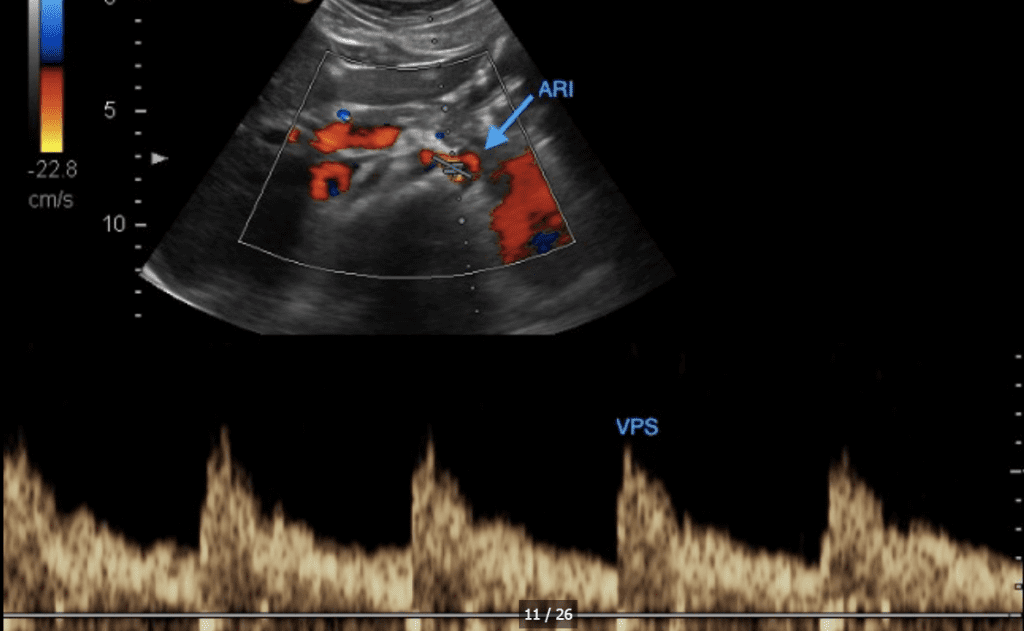

DOPPLER RENAL DE ALTA RESISTENCIA Y FLUJO REVERSO EN UN PACIENTE CON PERSISTENCIA DEL DUCTUS ARTERIOSO CON REPERCUSION HEMODINAMICA.

SHOCK CARDIOGENICO SECUNDARIO A SOBRECARGA HIDRICA DEBIDO A PERSISTENCIA DE DUCTUS ARTERIOSO GRANDE